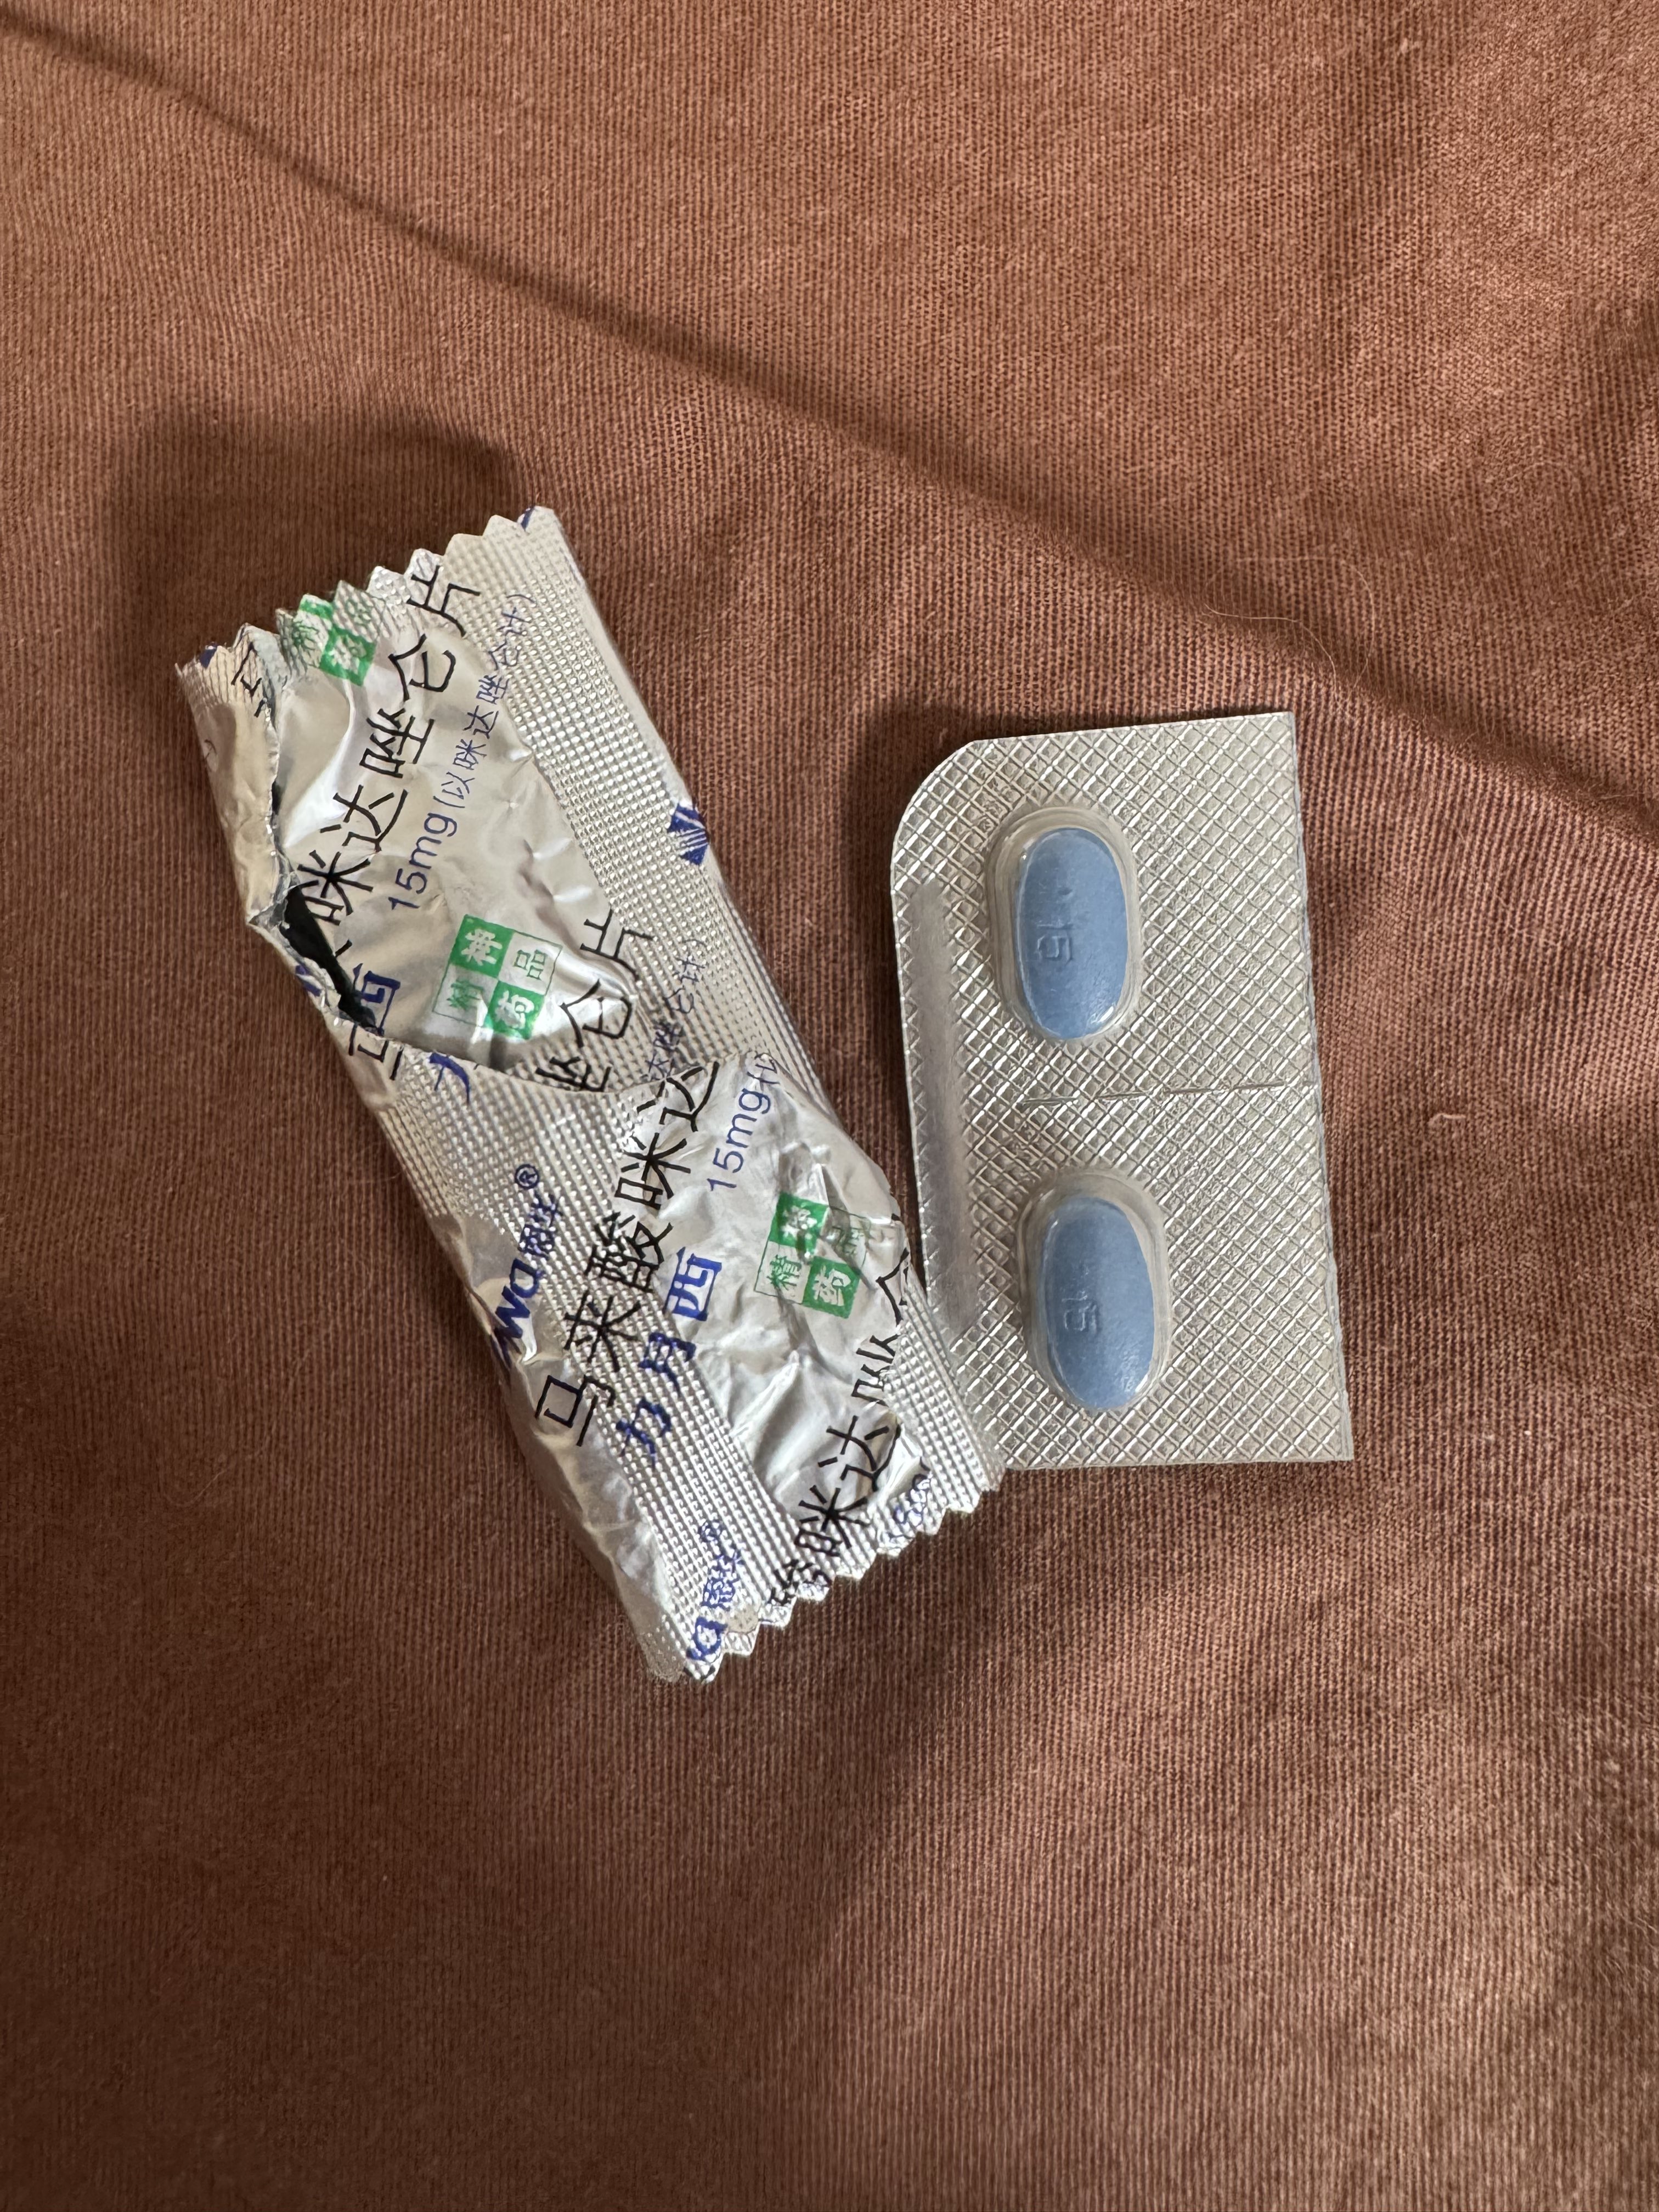

好家伙唑吡坦又骗我吃药了还顺带上了个失忆状态,这下子知道是谁干的了。吃auv之后dxm清除得特别慢...让我感觉要从此告别了的程度,加上我基因检测本来cyp2d6就是中速代谢,这个尾巴就被拖的特别长